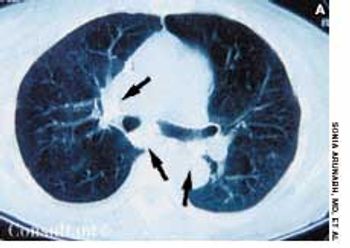

A 52-year-old woman was admitted tothe hospital with progressive shortnessof breath of 2 days’ duration. Bronchialasthma had been diagnosed 6 monthsearlier; inhaled corticosteroids, bronchodilators,and leukotriene antagonistswere prescribed. Despite aggressivetreatment, the patient’s dyspneaand wheezing worsened.